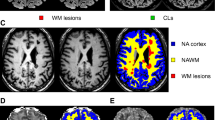

Mean kurtosis (MK), axial kurtosis (AK), radial kurtosis (RK), kurtosis fractional anisotropy (KFA), and the mean relative quantitative susceptibility mapping (mrQSM) values in the U-fiber region were compared between 49 pwRRMS and 48 healthy controls (HCs). The U-fiber were divided into upper and deeper groups based on the location. The whole brain volume, gray and white matter volume, and cortical thickness were obtained. The correlations between the mrQSM values, DKI-derived metrics in the U-fiber region and clinical scale scores, brain morphologic parameters were further investigated.

The decreased MK, AK, RK, KFA, and increased mrQSM values in U-fiber lesions (p < 0.001, FDR corrected), decreased RK, KFA, and increased mrQSM values in U-fiber non-lesions (p = 0.034, p < 0.001, p < 0.001, FDR corrected) were found in pwRRMS. There were differences in DKI-derived metrics and susceptibility values between the upper U-fiber region and the deeper one for U-fiber non-lesion areas of pwRRMS and HCs (p < 0.05), but not for U-fiber lesions in DKI-derived metrics. The DKI-derived metrics and susceptibility values were widely related with cognitive tests and brain atrophy.